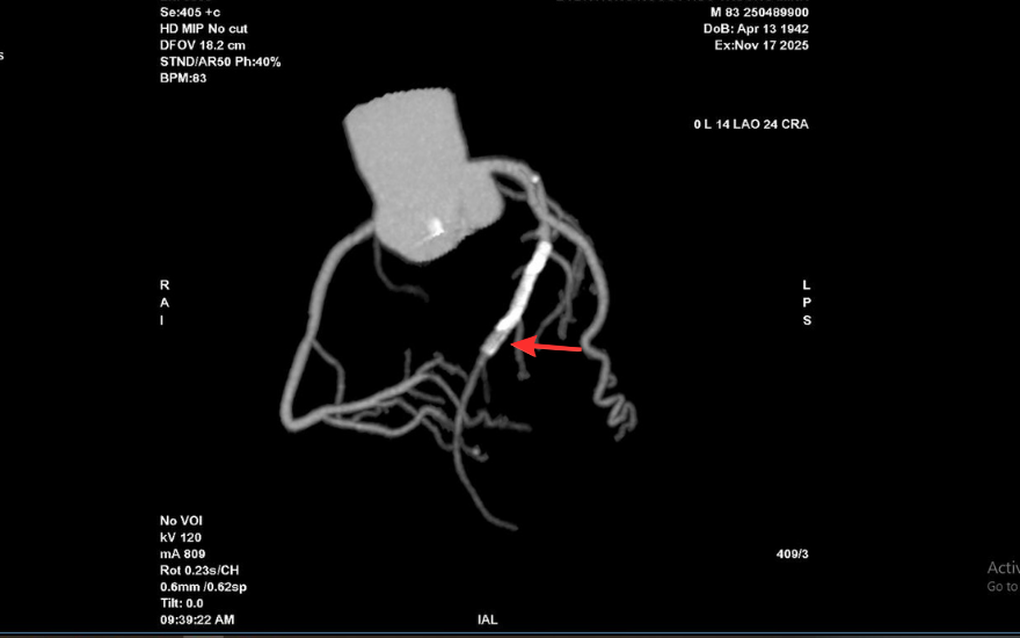

Tại Bệnh viện Đa khoa (BVĐK) Hồng Ngọc, kết quả chụp CT 2.560 lát cắt cho thấy tình trạng nghiêm trọng hơn nhiều so với biểu hiện ban đầu: mảng xơ vữa lan rộng gây hẹp nặng đoạn đầu động mạch liên thất trước và gần như làm tắc hoàn toàn lòng stent cũ. Đây là dấu hiệu cho thấy nguy cơ biến chứng tim mạch cấp tính có thể xảy ra bất cứ lúc nào nếu không được can thiệp kịp thời.

Vị trí hẹp khít trong lòng stent cũ của ông T trên hình chụp CT mạch vành 2.560 lát cắt (Ảnh: BVCC).

Kết quả chụp mạch vành qua da trước can thiệp cho thấy mức độ tổn thương của ông T. nghiêm trọng hơn dự kiến. Lòng stent cũ tái hẹp tới 99%, trong khi đoạn mạch phía trước vị trí đặt stent cũng hẹp khoảng 90%, khiến dòng máu nuôi tim bị chậm đáng kể.